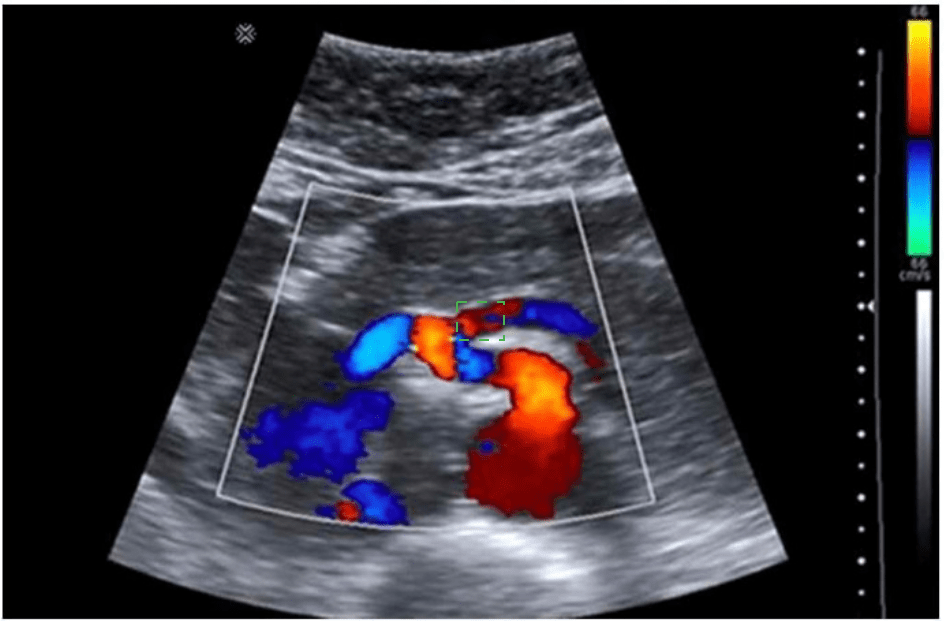

The absence of which sonographic finding indicates the acute process depicted in these images?

A ultrasound image of a person's body